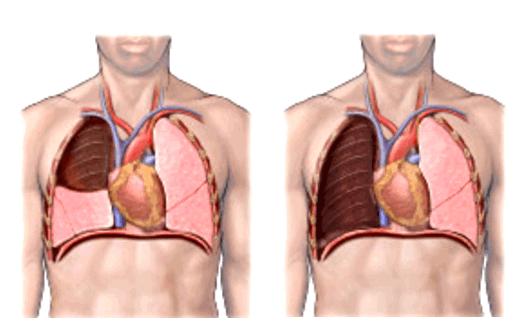

Рис. 1. Эхограмма. Кистозное образование правой почки. Гистологически - почечно-клеточная кистозная карцинома.

Многокамерное образование неправильной формы, с неровной толстой стенкой, с вкраплениями кальция, множественные перегородки с локальными утолщениями. Выраженная неоднородность внутренней эхоструктуры в виде чередования гипо-, изо- и гиперэхогеных участков.